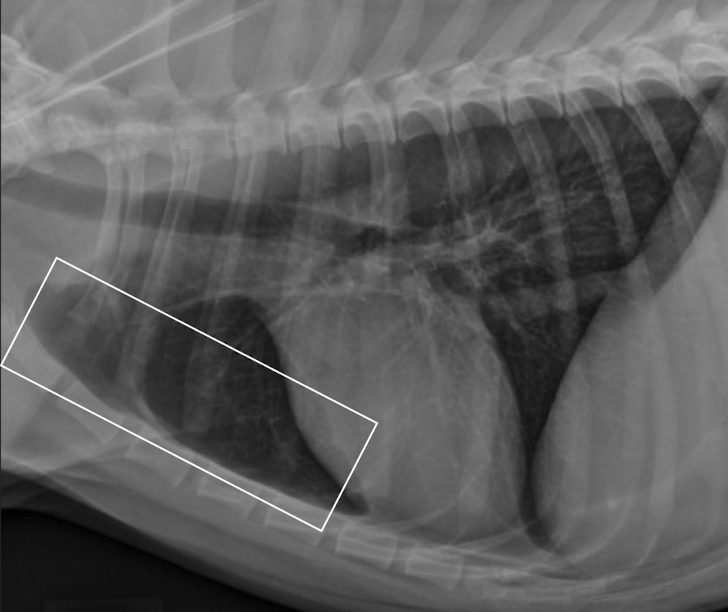

what is this showing

A

left: enlargment of middle tracheobronchial Lymph node → ventral displacement of carina

right: left atrial enlargmentdorsal displacement of carina

both will show bowing of the mainstem bronchi on VD (cowboy) and double opacity sign